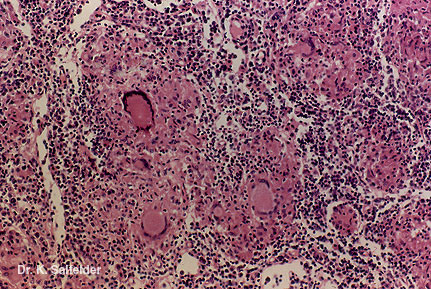

Abb. 9,32: Histoplasmose

Eine granulomatoese Reaktion und Granulome sind in der Lunge in spaeteren Entwicklungsphasen haeufig. HE-Faerbung